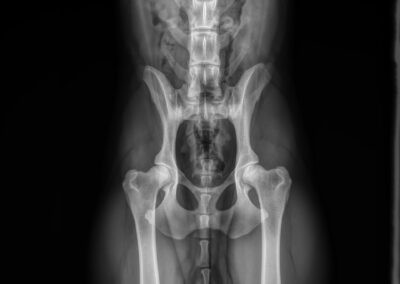

HD: A

ED: vrij